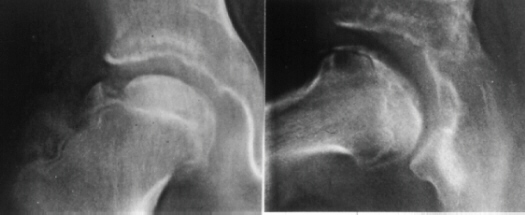

K.B.. 12-year-old boy. B.W. 63 kg(139 Ib.) . Perthes disease.

He had right hip pain and limping for seven weeks. When he was

first seen at University Hospital of Niigata, the right femoral

head was deformed already and collapsed slightly on X-ray.

The lateral part of the femoral head showed an impingement lesion.

Because good sphericity of the posterior part of the femoral head

was still preserved,

Sugioka's rotational osteotomy was advised. Pre-operative range

of motion was flex.90, abd.35, e.r. 40, and i.r. 15. The femoral

head was anteriorly rotated by 75 degrees and varus angulation

by 15 degrees was made.